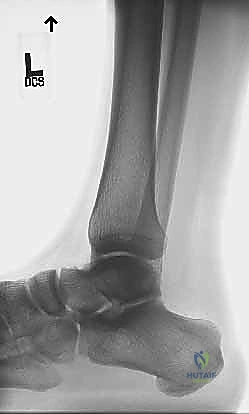

رغم أن الفحص السريري كافٍ غالباً، إلا أن التصوير الطبي يلعب دوراً مهماً في تقييم حجم التمزق والتخطيط الجراحي:

1. الموجات فوق الصوتية (Ultrasound): فحص ديناميكي ممتاز، سريع وغير مكلف، يُظهر بوضوح الفجوة بين نهايتي الوتر الممزق ويسمح بتقييم حركة نهايات الوتر أثناء تحريك القدم.

2. الرنين المغناطيسي (MRI): هو التصوير الأدق والأشمل. يوفر صوراً عالية الدقة تظهر مكان التمزق بدقة متناهية، المسافة بين نهايتي الوتر (Gap size)، جودة الأنسجة المتبقية، ووجود أي تنكس مزمن (Tendinosis) مصاحب. هذا يساعد الدكتور هطيف في تحديد ما إذا كانت تقنية "صندوق الهدايا" هي الأنسب أو إذا كانت الحالة تتطلب تطعيماً إضافياً للوتر.